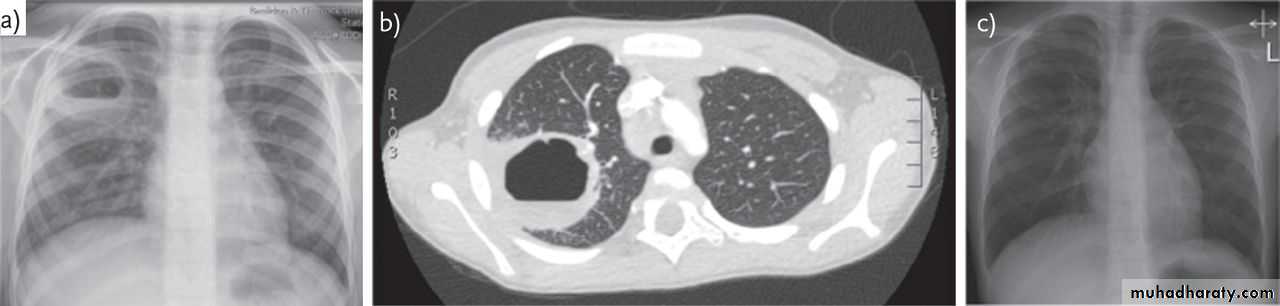

1-CXR:

PA and lateral views show effusion, air fluid level

• 6-CT scan

CXR : Air fluid level is only seen in upright filmCT san : clarify the diagnosis when the CXR is equivocal